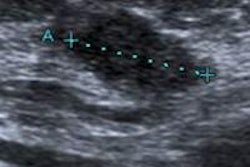

While early elastographic methods relied on manual compression and decompression applied by the examiner, VTIQ automates the tissue compression process to improve examiner independence and reproducibility, according to Dr. Michael Golatta, from the breast unit at the University of Heidelberg in Germany, and colleagues. The probe then generates a longitudinal push pulse that causes minimal localized displacement and is tracked by a detection pulse.

Because the speed of the shear waves propagating through the tissue is proportional to the stiffness of the tissue, a colored map in the region of interest (ROI) gives information on the tissue stiffness in the ROI, according to the authors.

VTIQ image of a healthy breast showing fatty tissue (1.38 m/sec) and parenchyma (3.33 m/sec). Image courtesy of Dr. Michael Golatta.The comparison of mean VTIQ values of parenchyma and fatty tissue in more and less dense breasts (ACR 1 + 2 versus ACR 3 + 4 breasts) yielded no statistically significant difference, the researchers found.